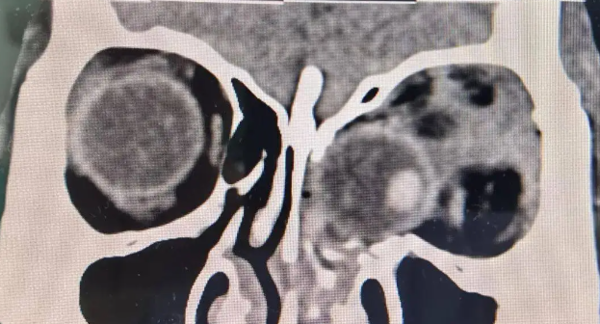

Sự việc hi hữu xảy ra khi người phụ nữ họ Hoàng (50 tuổi) đang leo cầu thang tại Quý Châu (Trung Quốc). Do bất cẩn, bà đã bị ngã từ tầng 3 xuống, gây đau đớn toàn thân và mất thị lực mắt trái. Bà được đưa đến Bệnh viện trực thuộc Đại học Y khoa Quý Châu cấp cứu. Tại đây, các bác sĩ phát hiện nhãn cầu trái của bà đã bị rơi vào khoang mũi, một tình huống vô cùng nguy hiểm.

Bác sĩ Dương Hạ, Phó Giám đốc Khoa Mắt, cho biết: "Bệnh nhân nhập viện trong tình trạng thành trong và dưới ổ mắt trái bị gãy xương, nhãn cầu bị lệch vào khoang mũi, kẹt giữa xoang sàng trái và xoang hàm trên. Xung quanh nhãn cầu đầy mảnh xương vỡ, nhãn cầu bị biến dạng và dây thần kinh thị giác bị xoắn...". Nhận thấy thời gian vàng để cứu mắt chỉ còn chưa đầy 48 tiếng, đội ngũ y bác sĩ đã quyết định phẫu thuật khẩn cấp.

Ê-kíp phẫu thuật do bác sĩ Dương Hạ dẫn dắt đã tiến hành ca phẫu thuật mở ổ mắt trái kết hợp nội soi mũi để đưa nhãn cầu trở về vị trí ban đầu. Bác sĩ Dương Hạ chia sẻ thêm: "Chúng tôi đã tỉ mỉ làm sạch các mảnh xương vỡ trong ổ mắt, loại bỏ máu tụ trong khoang mũi, đồng thời mở rộng không gian khoang mũi. Sau đó, chúng tôi đã mở một cửa sổ xương trên ổ mắt và cẩn thận đưa nhãn cầu trở lại vị trí cũ, tránh gây tổn thương thêm cho nhãn cầu".

Do tình trạng gãy xương ổ mắt nghiêm trọng, các bác sĩ đã sử dụng vật liệu chuyên dụng để tái tạo lại thành ổ mắt, giúp nhãn cầu không bị rơi vào khoang mũi một lần nữa. Ca phẫu thuật kéo dài gần 4 giờ đồng hồ đã diễn ra thành công. Nhờ phương pháp phẫu thuật ít xâm lấn, bệnh nhân không để lại sẹo trên mặt.